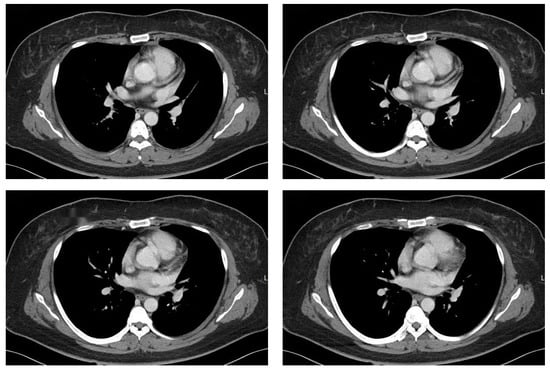

- Shi, J.; Bao, G.; Hong, J.; Wang, S.; Chen, Y.; Zhao, S.; Gao, A.; Zhang, R.; Hu, J.; Yang, W.; et al. Deciphering CT texture features of human visceral fat to evaluate metabolic disorders and surgery-induced weight loss effects. eBioMedicine 2021, 69, 103471. [Google Scholar] [CrossRef]

- Dadson, P.; Rebelos, E.; Honka, H.; Juárez-Orozco, L.E.; Kalliokoski, K.K.; Iozzo, P.; Teuho, J.; Salminen, P.; Pihlajamäki, J.; Hannukainen, J.C.; et al. Change in abdominal, but not femoral subcutaneous fat CT-radiodensity is associated with improved metabolic profile after bariatric surgery. Nutr. Metab. Cardiovasc. Dis. 2020, 30, 2363–2371. [Google Scholar] [CrossRef]